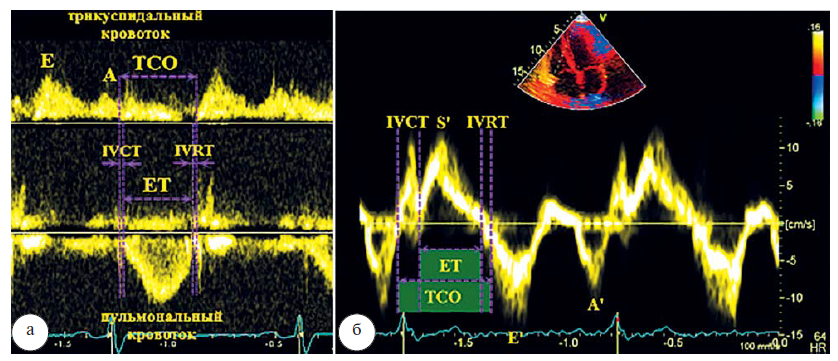

Некоторые исследователи полагают, что оценка функции желудочков может быть выполнена с помощью индекса работы миокарда (MPI). Рассчитывается как соотношение суммы времени изоволюметрического расслабления (IVRT) и изоволюметрического сокращения (IVСT) ко времени выброса (ET).

Правосторонний MPI может быть получен двумя способами, с помощью импульсного и тканевого допплеровских режимов (рис. 10 а, б). Использование тканевого допплеровского режима проще, так как все временные интервалы измеряются во время одного сокращения при направлении импульса на латеральную часть трикуспидального кольца. Эта методика доступна для большинства пациентов как с трикуспидальной регургитацией, так и без нее, является легко воспроизводимой, не зависит от ограничений сложной геометрии ПЖ. Одновременно могут быть измерены другие показатели функции правых камер– систолическая скорость экскурсии (S’), скорость раннего диастолического движения (E’) и скорость позднего диастолического движения (A’) на одном изображении. Значения MPI >0,43 для импульсного и >0,54 для тканевого допплеровского режима могут свидетельствовать о дисфункции ПЖ.

Рис. 10. Измерение MPI ПЖ в импульсном допплеровском (а) и в тканевом допплеровском режимах (б)

Следует учитывать, что MPI недостоверен при разных R–R интервалах (например, фибрилляция предсердий), при повышении давления в правом предсердии (например, при инфаркте ПЖ), так как сокращается IVRT, что приводит к занижению MPI.